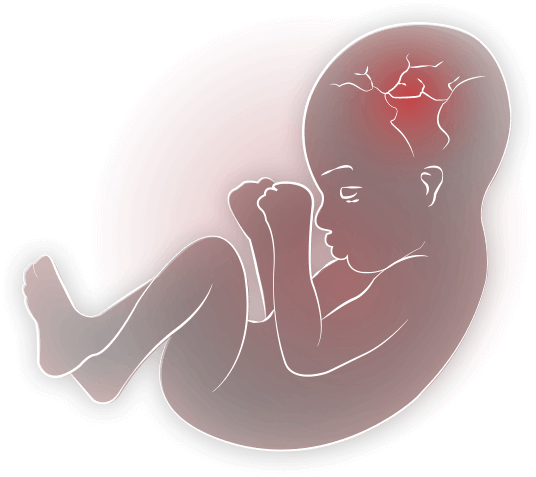

Иконки и символы, связанные с эмбрионом